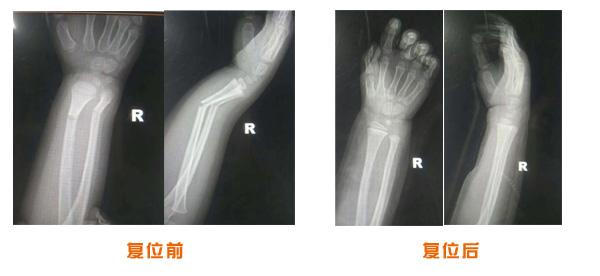

肥城市安駕莊梁氏骨科醫院是一所以梁氏手法正骨配合膏藥為特色的現代化??漆t院。

梁氏骨科術始創于清雍正年間,歷經八代,至今已有三百年歷史。據1929年泰安縣志載“梁瑞圖先生,字增生,號蓮峰,安駕莊人,精岐黃并發明接骨,凡跌打車凡跌打車軋皮不破而碎骨者......【詳細】 |